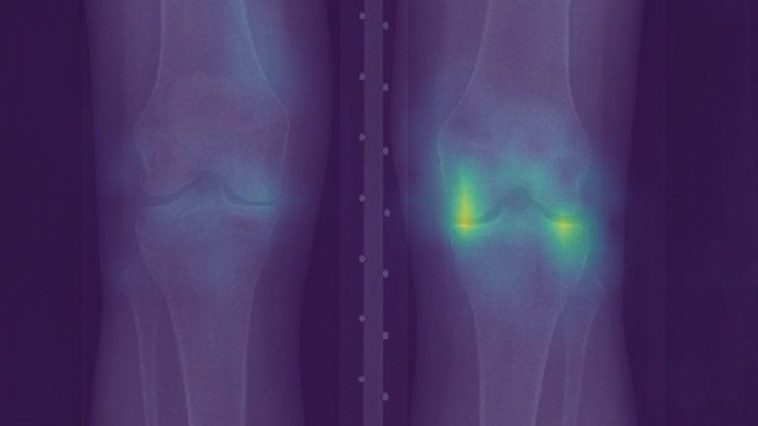

Researchers used artificial intelligence techniques to analyse knee X-rays to “predict patients’ experienced pain” for those suffering from osteoarthritis of the knee.

The computer analysis could pick up things that a radiologist might miss.

But the algorithm indicated that the cases were less similar than they appeared.

It took account of additional undiagnosed features that would be overlooked by doctors employing the commonly used radiographic grading systems.

And because patients who reported severe pain and scored highly on the algorithm’s own measure, but low on the official grading systems were more likely to be black, it suggests traditional diagnostics may be ill serving the community.

“What we found is that the algorithm was able to explain more of the pain that everyone was feeling,” said Prof Obermeyer.

“So it just did a better job at finding things that hurt in everyone’s knees.

“The benefit of that additional explanatory power was particularly great for black patients.”